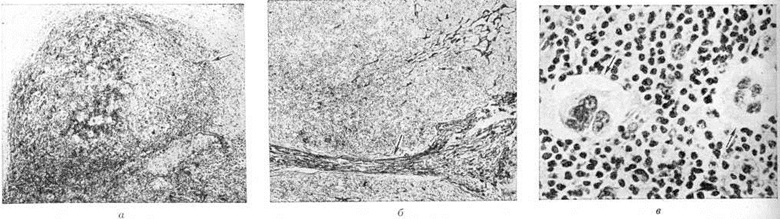

Микропрепараты: Лимфогранулематоз и Нодулярный Склероз